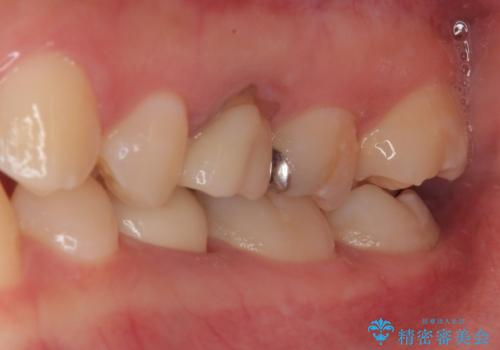

- 左下の乳歯に虫歯ができたので銀歯も外してやり替えたいとのことで来院された患者様です。

レントゲン上で金属の詰め物(メタルインレー)の下に虫歯を認めた為、オールセラミッククラウンでの治療と、乳歯なので予後を考えインプラントによる補綴治療もご提案しましたが、患者様の強い希望によりオールセラミッククラウンでの治療となりました。

拡大鏡視野下で、金属の詰め物(メタルインレー)、虫歯の除去を行い、オールセラミッククラウンに適した形に整えました。

治療後特に問題もなく見た目、噛み合わせともに満足していただけました。